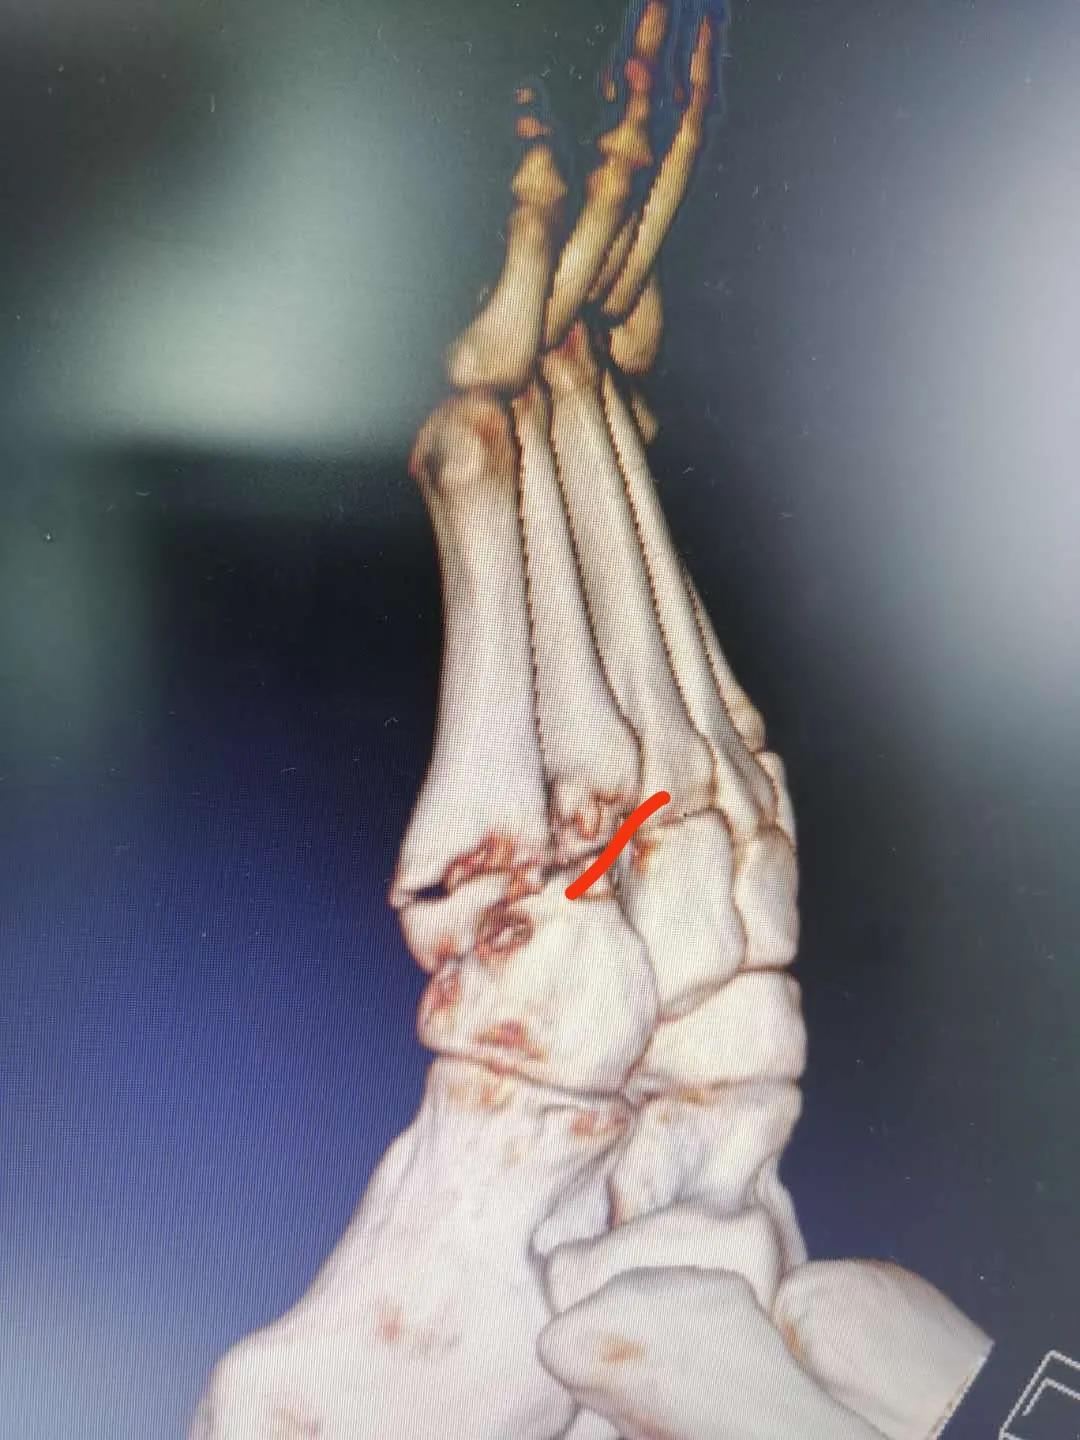

看片子骨缝比较大了,有点移位,而且中间崩碎了一块,一直找不到,后来复查才发现那个碎片掉落在骨缝当中了

此图可以看见中间碎片在骨缝里面